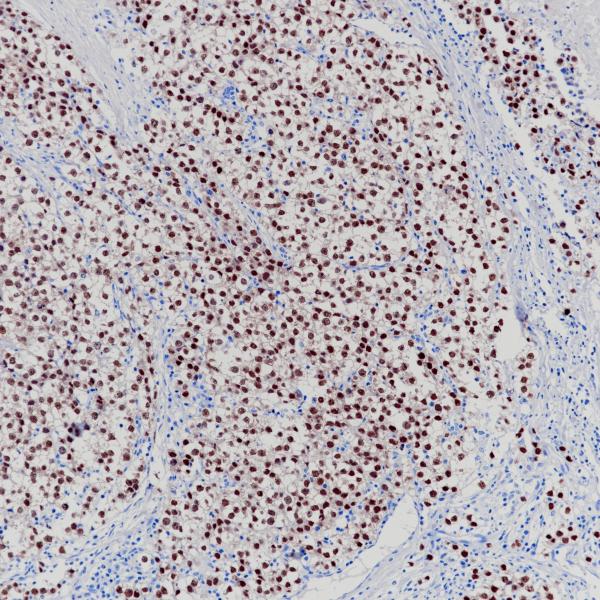

Oct 3/4

BP6164

OCT-3/4

BP6282

Olig2

BP6167